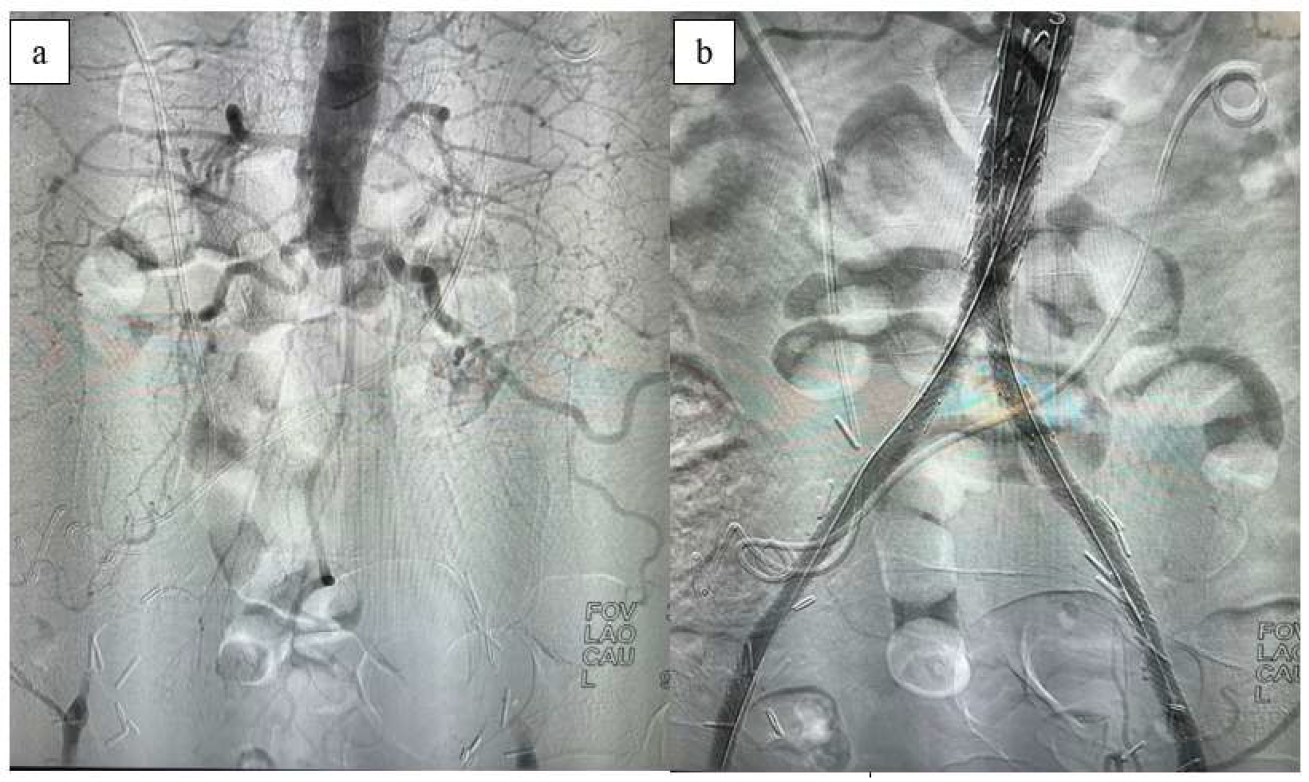

The primary patency rate was approximately 98% within the first 6 months but declined to around 85% by the end of the 2-year follow-up period. The secondary patency rate was observed to be 92.5% at the conclusion of the follow-up (Figure 4). During the follow-up, stenosis exceeding 50% developed in four patients. Of these, one patient underwent bilateral iliac percutaneous transluminal angioplasty (PTA), while the others had iliac-femoral PTA and a stent placed in the distal external iliac artery. Additionally, selective thrombolytic therapy was administered to one patient at 16 months due to thrombus formation in the common iliac artery.

Figure 4. Kaplan–Meier survival analysis showing patency curves of patients treated with CERAB (blue: primary patency; green: secondary patency; red: primary assisted patency). Differences between groups were evaluated at significance level of p < 0.05.